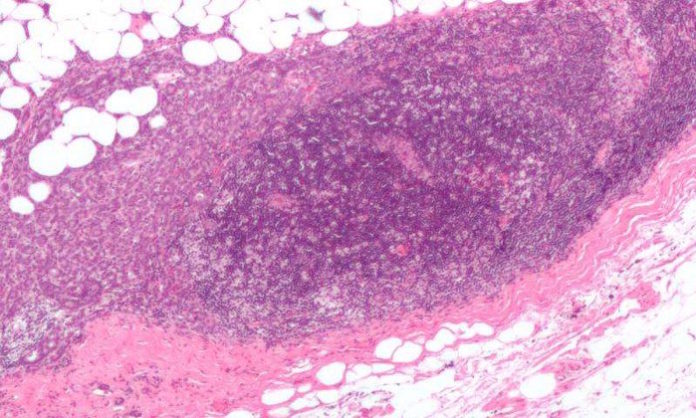

Using two commercially available breast cancer cell lines obtained from women with estrogen-receptor-positive breast cancer, the research team exposed the cancer cells to varying strengths of BPS or to an inactive substance as a control.

The investigators also treated the breast cancer cells with estradiol (estrogen) and found that BPS acted like estrogen in multiplying breast cancer cells, Dinda said. Compared with the control, BPS heightened the protein expression in estrogen receptor and BRCA1 after 24 hours, as did estrogen. After a six-day treatment with BPS, the breast cancer cells in both cell lines reportedly increased in number by 12 percent at the lowest dose (4 micromolars) and by 60 percent at 8 micromolars.

The research team then blocked the BPS-induced proliferation of breast cancer cells by treating the cells with anti-estrogen drugs, which are used to block estrogen’s action onto estrogen binding proteins (estrogen receptors) in breast cancer cells.